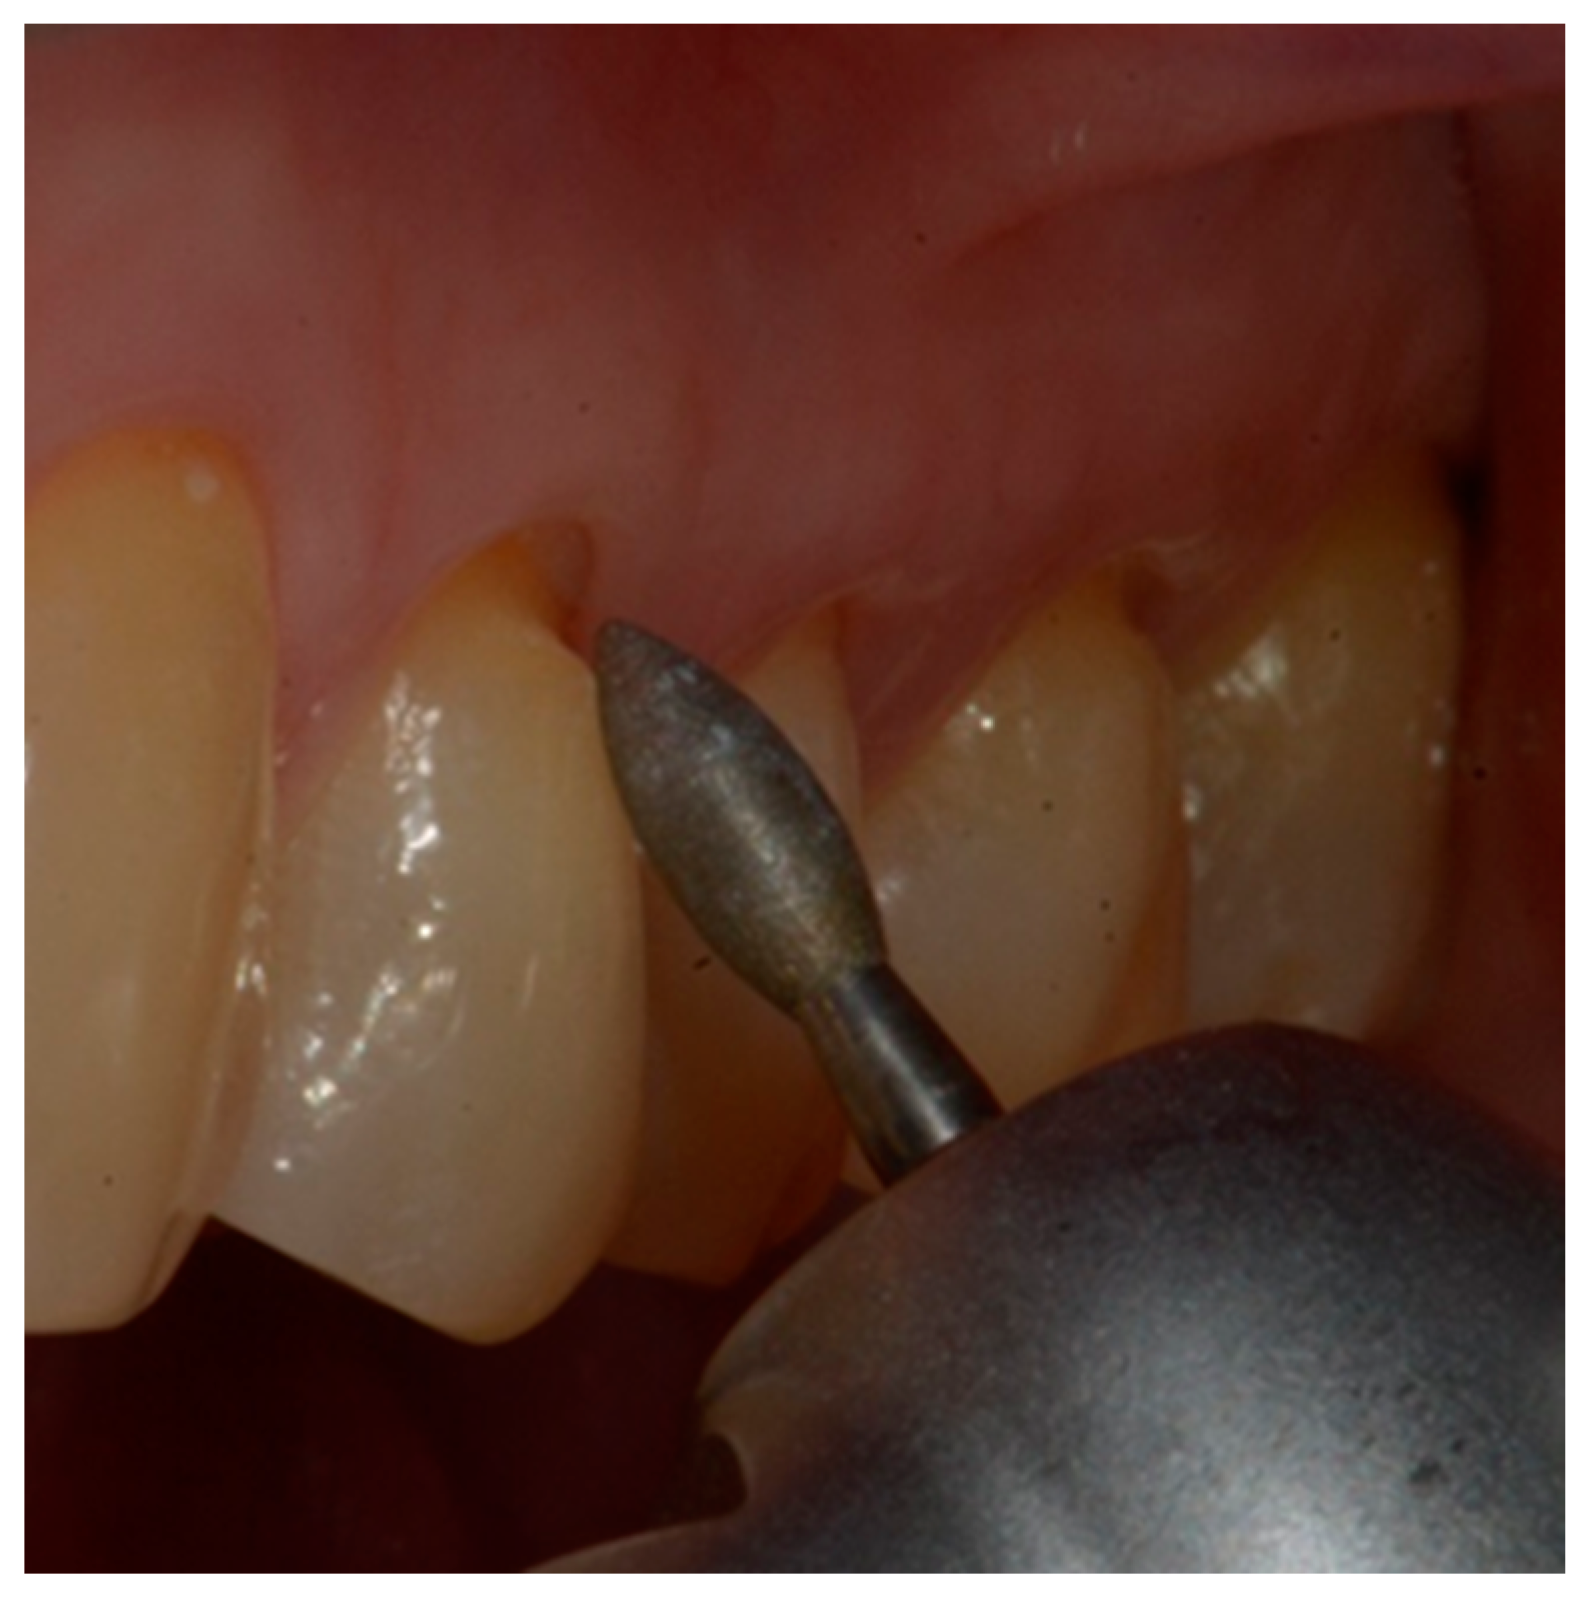

- mechanical cleaning with a diamond bur of the bottom of the cavity to expose new dentin.

- definition of a small bevel of the enamel (mini-chamfer) in correspondence with the coronal perimeter of the lesion with fine-grained diamond burs to favor the adhesion processes and the mimicry of the restoration and to give sufficient thickness to the most coronal composite (Figure 4).